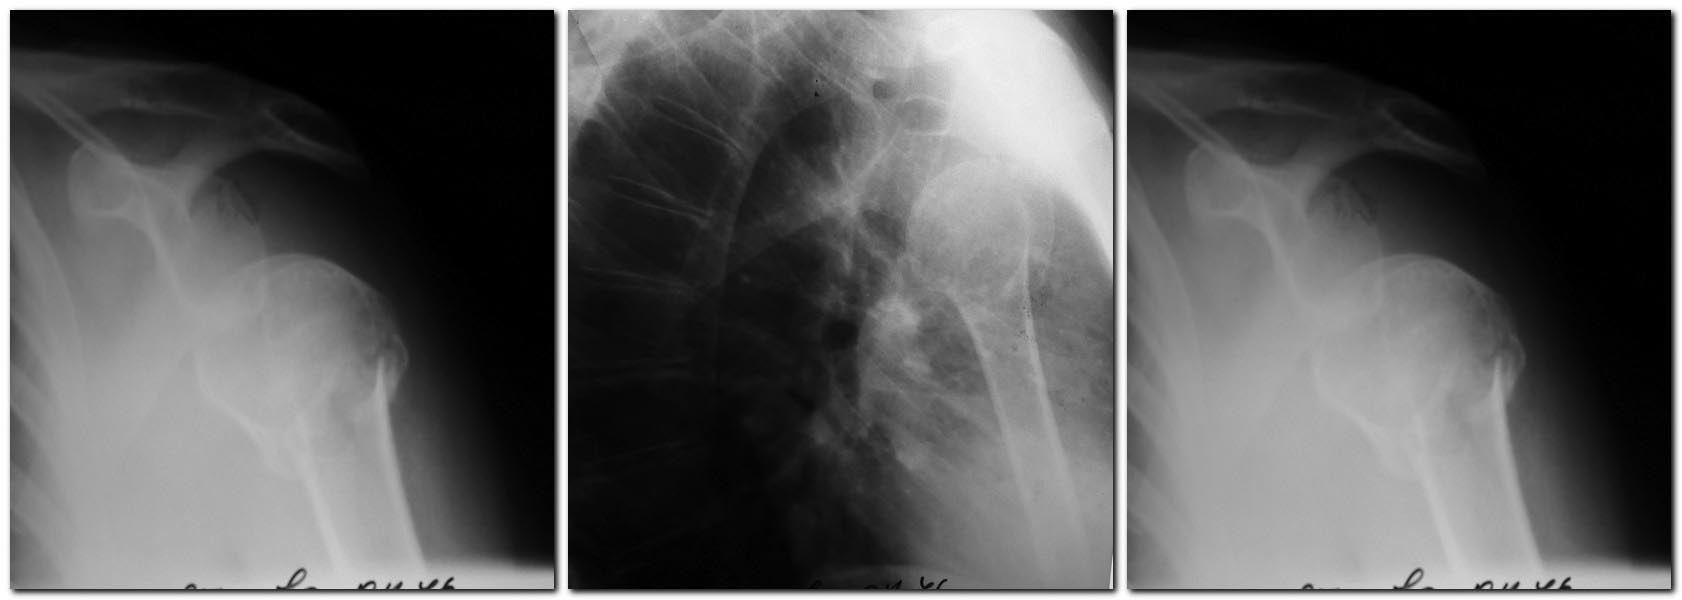

Уважаемые коллеги!

Планирую ревизию надостной мышцы, при ее разрыве -шов. Синтез

проксимальным гвоздем (доступна и пластина LCP). Время с момента

травмы-2 недели. Правильна ли тактика? Какие подводные камни могут

встретиться? Допустима ли трансартикулярная фиксация спицами в случае

неустранимого подвывиха? Спасибо.